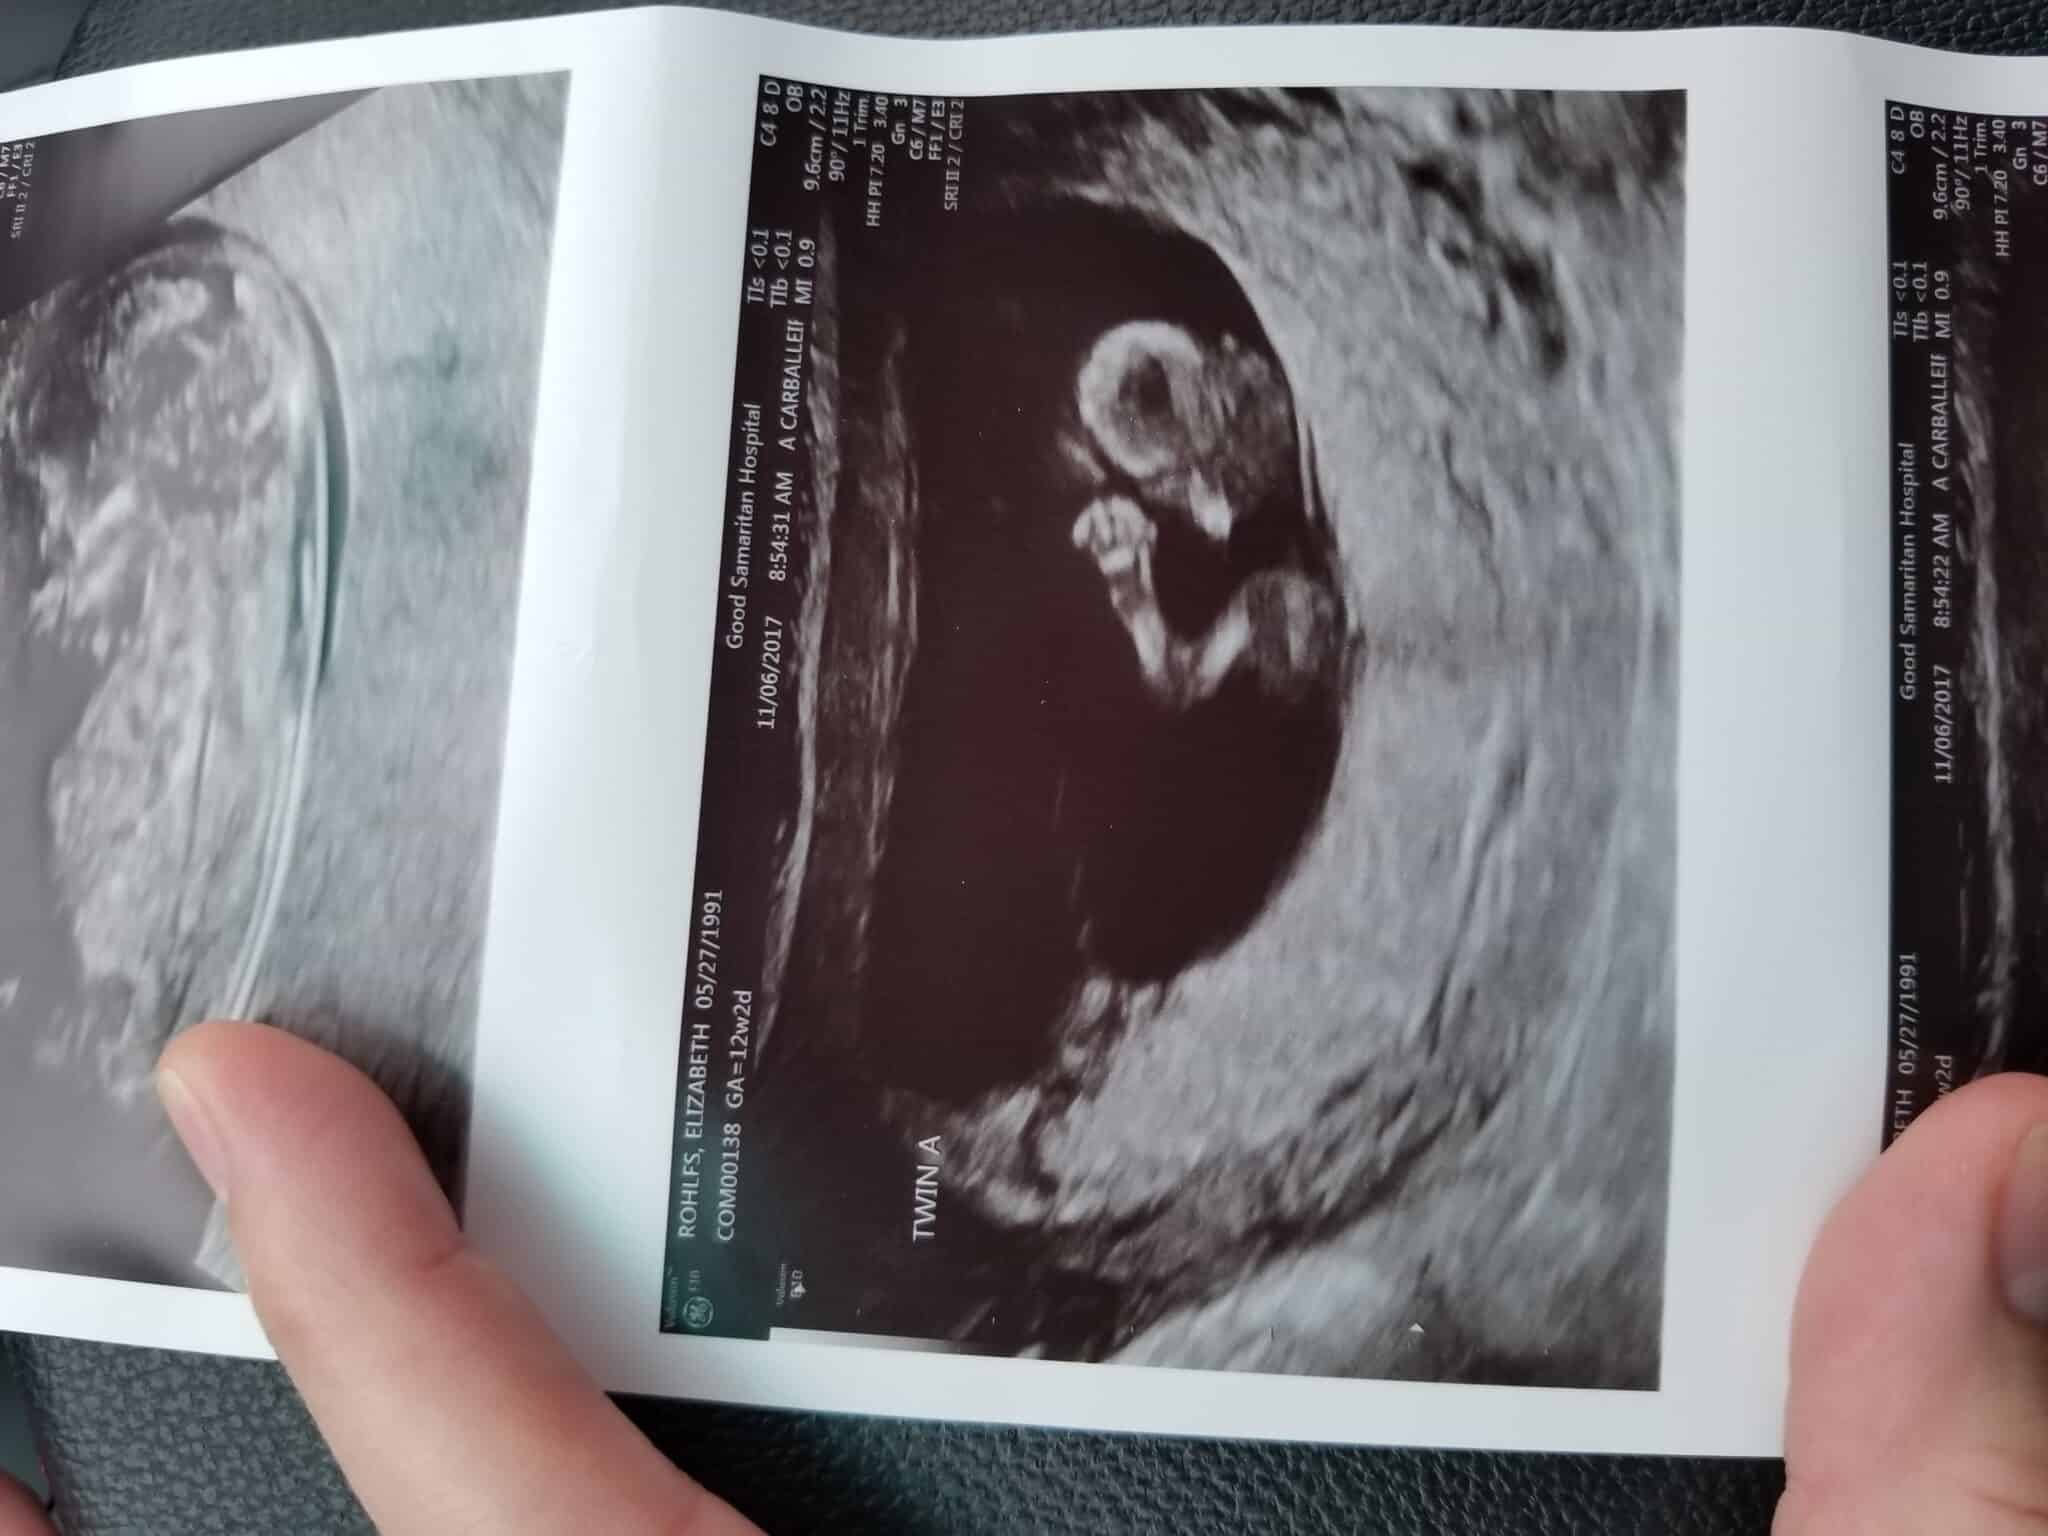

Ultrasound Photos at 12 Weeks Pregnant With Twins